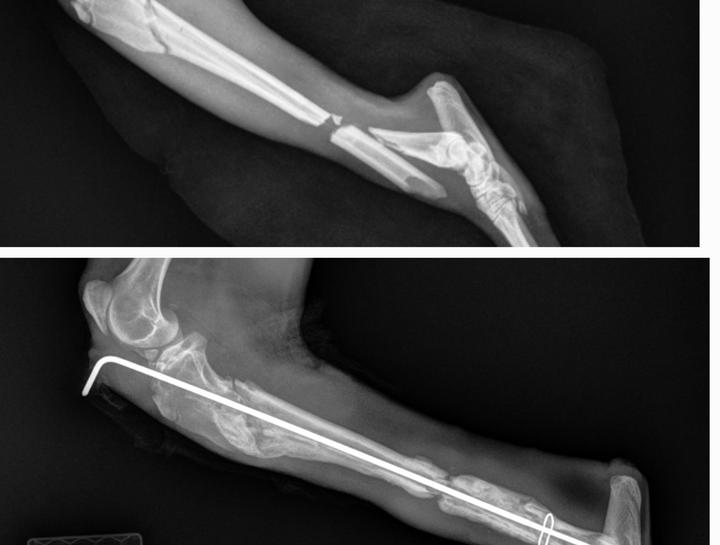

Orthopedic Pet Surgery

Surgeries for bone or joint repair.